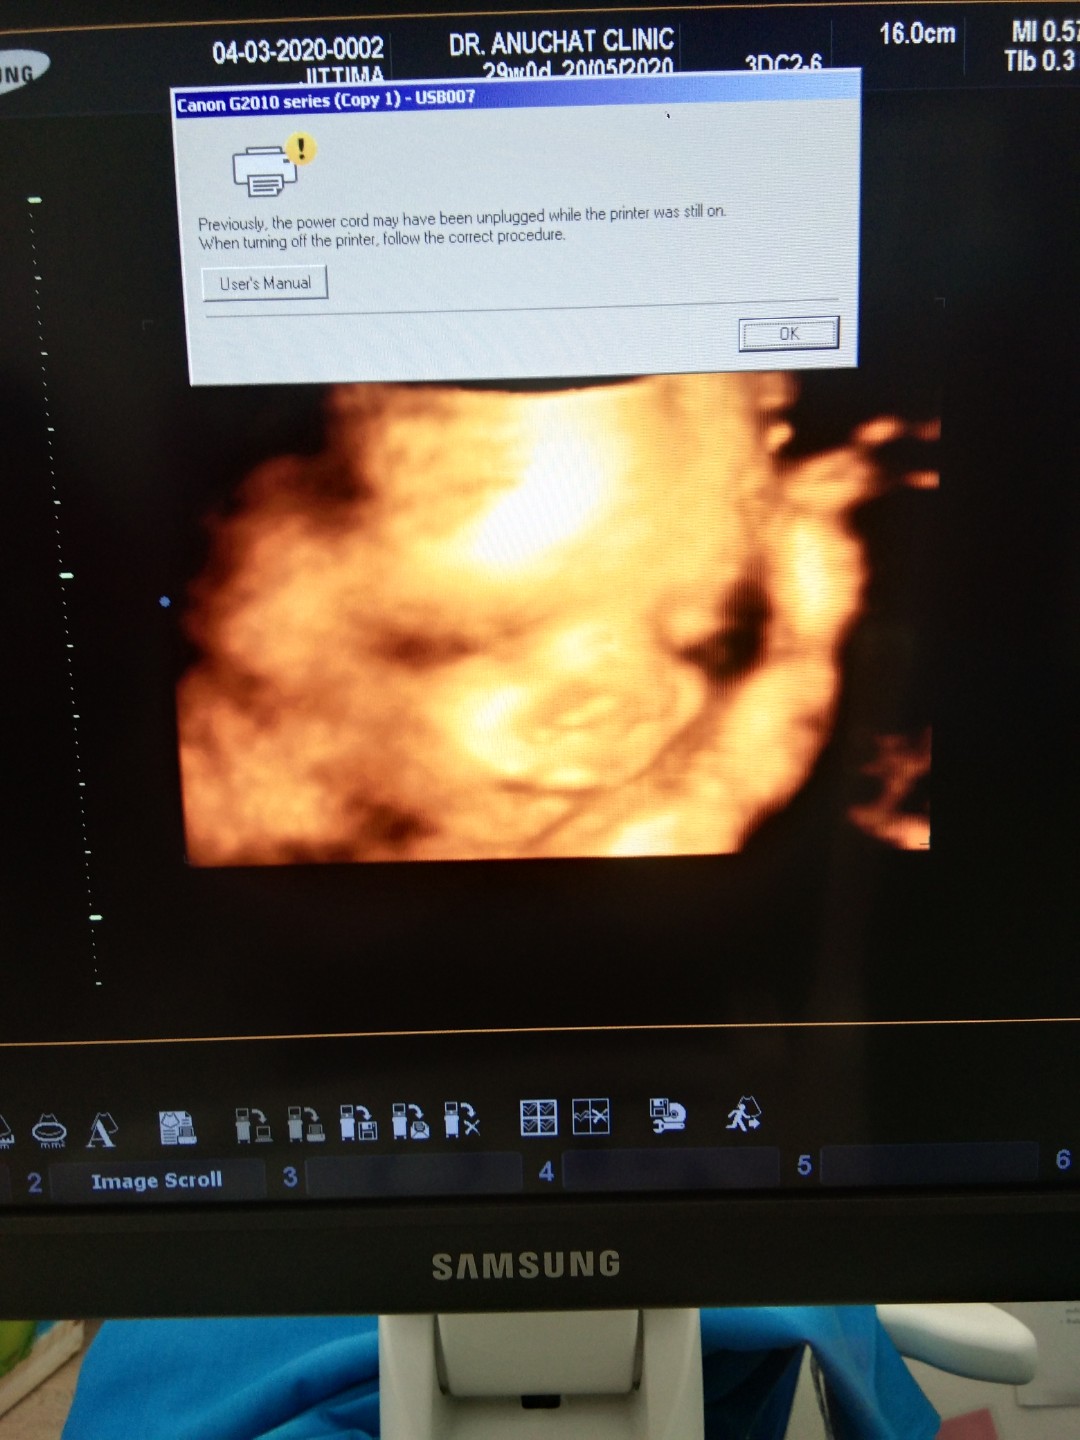

20 พ.ค. ครับผม